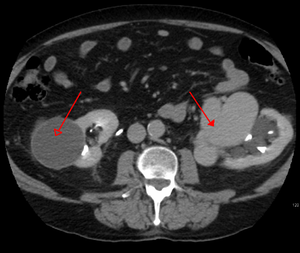

يتم تشخيص التشوه الشرياني الوريدي بشكل أساسي من خلال طرق التصوير التالية:

- التصوير المقطعي المحوسب (CT) هو عبارة عن أشعة سينية غير باضعة لعرض الهياكل التشريحية داخل الدماغ لاكتشاف الدم في الدماغ أو حوله. تتضمن تقنية أحدث تسمى تصوير الأوعية المقطعية المحوسبة حقن التباين في مجرى الدم لعرض شرايين الدماغ. يوفر هذا النوع من الاختبارات أفضل صور الأوعية الدموية من خلال تصوير الأوعية والأنسجة الرخوة من خلال التصوير المقطعي المحوسب.

يمكن أن تحدث التَشوّهات الشريانية الوريدية في أجزاء مختلفة من الجسم:

- كلية[13]